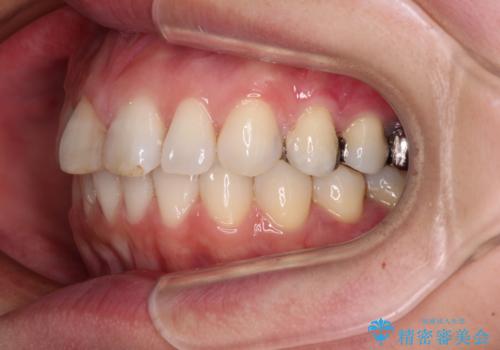

- 前歯のデコボコを治したいとのことで来院された患者様です。

上下顎ともに歯列全体の後方移動とIPR(歯と歯の間を削る)によってデコボコが解消するように設計し、インビザラインにより治療を行うこととしました。

しっかりと装着時間を守ってくださったのですが、途中妊娠にともなう悪阻や出産といったイベントがあり、予定よりも治療期間が長くなりました。